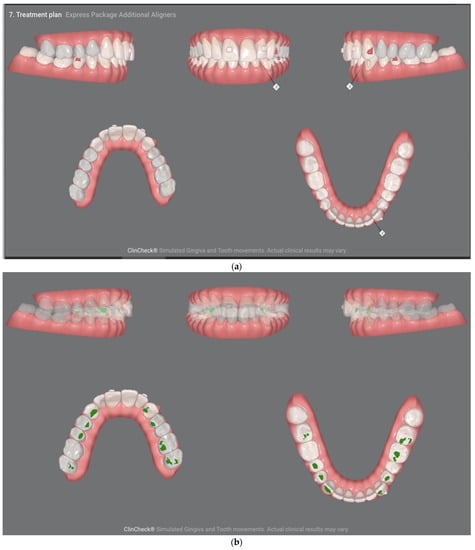

- Pretreatment occlusion scan using the iTeroTM 5.0 scanner, extracted into OrthoCAD 5.9.1.50 software (Align Technology, San Jose, CA, USA) (Figure 4), extra- and intraoral images taken with the Invisalign Practice App (Align Technology, San Jose, CA, USA) and pantomogram (Figure 5). Based on the iTeroTM 3D scan (Align Technology, San Jose, CA, USA) and occlusal examination, it was decided to use the Invisalign® system (Align Technology, San Jose, CA, USA) with the Express 1 arch subtype—the shortest possible treatment with seven aligners (and seven additional aligners) involving only the upper arch because the aim was to eliminate the occlusal injury of one tooth by its intrusion and a change of the anterior–posterior and mesiodistal inclination. The first treatment plan was performed using the ClinCheck 6.0 software (Align Technology, San Jose, CA, USA), which assumed movements of tooth 21—the main movement was a palatal inclination of the crown by 4.4 degrees, a distortion by 3.3 degrees and an intrusion by 0.4 mm (Figure 6). The analysis of this plan showed that it was impossible to eliminate the traumatic occlusion when changing the position of only one tooth in the arch (Figure 7)—the analysis showed numerous abnormal occlusal contacts.

For this reason, the plan was changed, extending the orthodontic treatment to include the lower arch—a significant intrusion of the lower incisors and canines from 0.5 mm to 1.4 mm, distorotation up to 9.3 degrees and lingual inclination up to 5.5 degrees were planned. Translational axial movements and isolated root movements were also planned, including even 5-degree lingual torque movements (Figure 8a,b). The main focus was on the movements of the lower teeth due to the need to minimize the inevitable resorption of the root apex of tooth 21 (Figure 8c,d).

After using seven aligners, the patient was scanned again to continue treatment with the use of another seven aligners in order to achieve the best possible treatment results. The occlusion after the first part of the treatment (after the first seven aligners) is shown in Figure 9a,b. No occlusal overloads on the upper incisors are visible; thus, therapeutic success was achieved.

Figure 9.

(a) Occlusal condition before wearing additional aligners. (b) No occlusal overloads on the incisors are visible; thus, therapeutic success was achieved.

Subsequent aligners were used to calibrate the occlusion and obtain the aesthetic effect.